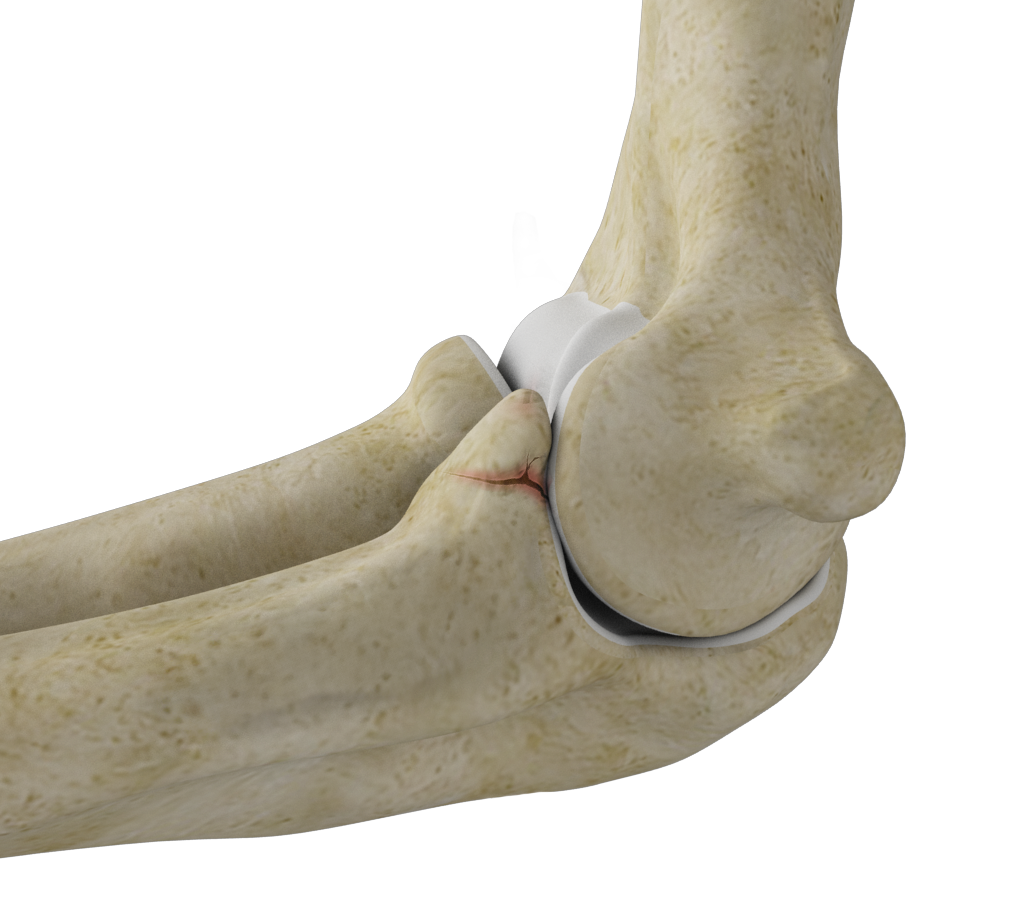

Elbow Anatomy

The elbow is a complex joint formed by the articulation of three bones – the humerus, radius, and ulna. The elbow joint helps in bending or straightening of the arm to 180 degrees and lifting or moving objects.